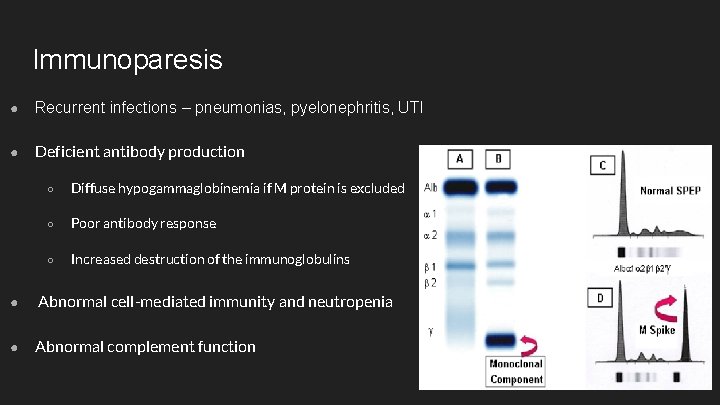

Immunoparesis ● Recurrent infections – pneumonias, pyelonephritis, UTI ● Deficient antibody production ○ Diffuse hypogammaglobinemia if M protein is excluded ○ Poor antibody response ○ Increased destruction of the immunoglobulins ● Abnormal cell-mediated immunity and neutropenia ● Abnormal complement function